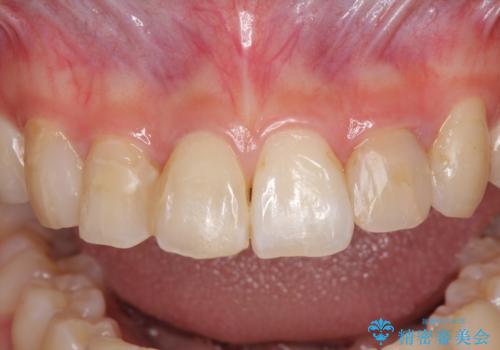

- コンポジットレジンによる治療で継ぎ接ぎだらけになってしまった前歯を綺麗にしたいとのことで来院された患者様です。

必要に応じて根管治療を行い、前歯6歯をオールセラミッククラウンで補綴することとしました。

治療途中に出産を迎えるため、下顎前歯のデコボコを部分矯正で改善し、上下前歯を綺麗に仕上げることとしました。